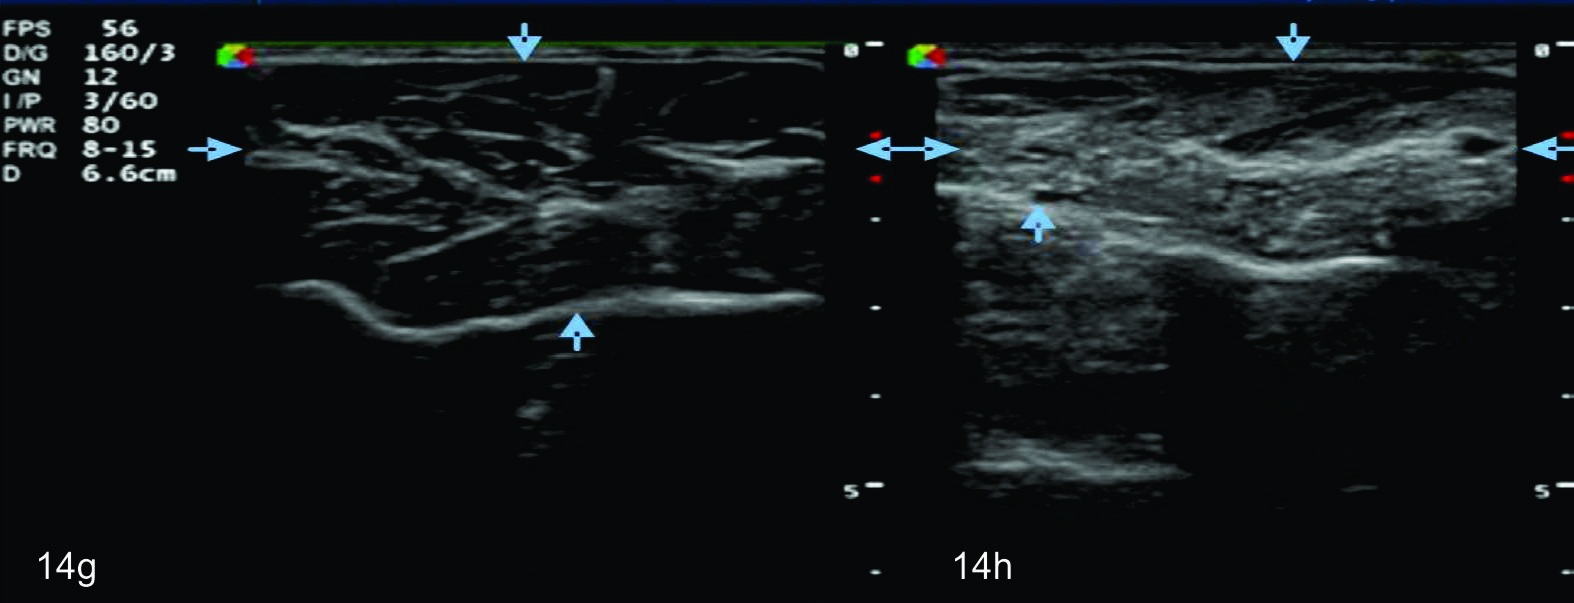

Figura 14 e, f, g y h

Lesión traumática del plexo braquial luego de accidente en moto.

EyF-Cortes comparativos a nivel de cara anterior de brazo derecho o afectado (E) y brazo izquierdo o sano (F), en donde se identifica la clara asimetría en el volumen y ecogenicidad de los planos musculares (flechas azules) en relación a cambios por atrofia. H- diáfisis humeral. GyH- Cortes comparativos a nivel de la cara anterior del antebrazo derecho o afectado (H) e izquierdo o sano (G), demuestra hallazgos similares. R- Diafisis radio, C- Diafisis cubito.